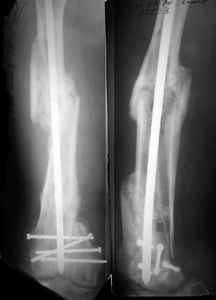

Attached are few examples from our Hospital:

Malpositioning is much too common (recurvatum, varus - valgus).

B. Fixation loosening: distal cutting of the nail, non-unions do happen (cases attached).

Locking Plating has more distal screws than any nail, fixed angles and provides much better fixation, especially in osteoporotic bone.

A new toy is more interesting and fashionable. And anyway it is not panacea, i have already seen presentations with LISS failures like the attached one presented by D.Seligson. And people also demonstrated incisions say that the method is not so LESS invasive as it supposed to be.